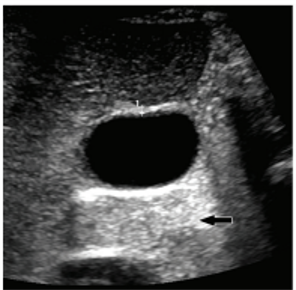

An artifact in this image is caused secondary to what property of the ultrasound waves?

attenuation

Shadowing artifact occurs secondary to the reflective and attentive properties of the imaged structure. As seen in this example, the gall bladder stone is highly attenuating and reflectiv3e leading to complete abscence of sound waves behind the stone.